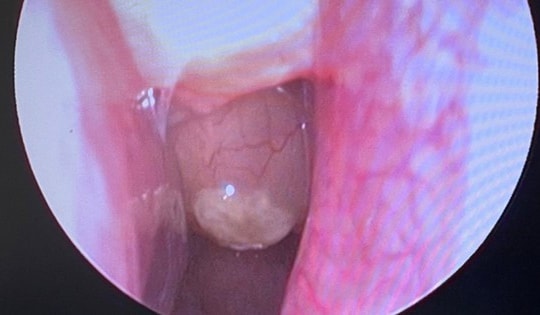

Bệnh viện Hữu Nghị cắt bỏ u tuyến tiền liệt 'khủng' 600 gram cho cụ ông 83 tuổi

31/10/2025 10:15

Các bác sĩ Khoa Ngoại – Tiết niệu, Bệnh viện Hữu Nghị vừa phẫu thuật thành công cho bệnh nhân nam 83 tuổi có tuyến tiền liệt kích thước "khủng" lên tới 600 gram – gấp hàng chục lần so với bình thường.